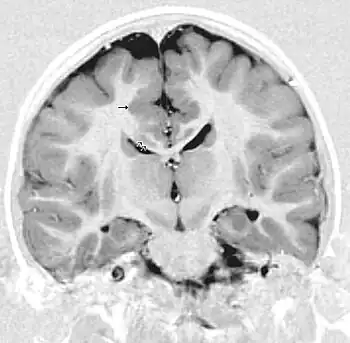

MRI of a child experiencing seizures. There are small foci of grey matter heterotopia in the corpus callosum, deep to the dysplastic cortex. (double arrows)

Gray matter heterotopia is a neurological disorder caused by gray matter being located in an atypical location in the brain.[1] Grey matter heterotopia is characterized as a type of focal cortical dysplasia. The neurons in heterotopia are otherwise healthy; nuclear studies have shown glucose metabolism equal to that of normally positioned gray matter.[2] The condition causes a variety of symptoms, but usually includes some degree of epilepsy or recurring seizures, and often affects the brain's ability to function.

Detection of heterotopia generally occurs when a patient receives brain imaging—usually an MRI or CT scan—to diagnose seizures that are resistant to medication. Correct diagnosis requires a high degree of radiological skill, due to the heterotopia's resemblance to other masses in the brain.